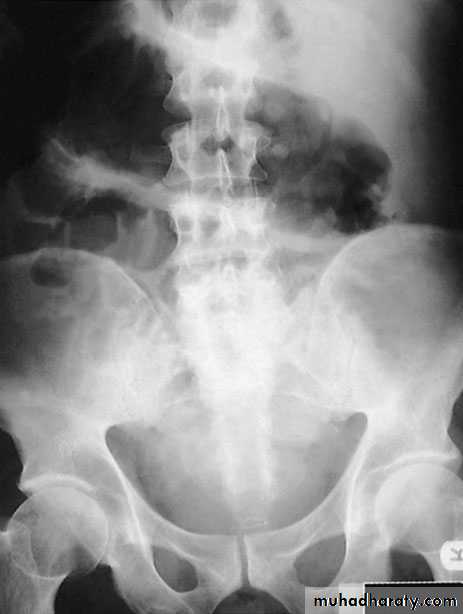

Complications of severe diseaseFulminating colitis and toxic dilatation (megacolon)Patients with severe disease should be admitted to hospital forintensive treatment. This occurs in 5–10% of patients. The patient will have severe rectal symptoms with systemic upset suchas weight loss and dehydration. In patients on intensive treatment such as steroids, there may befew symptoms. The diagnosis is confirmed by the presence on a plain abdominal radiograph of the colon with a diameter of more than 6 cm. The condition must be differentiated from dysentery, typhoid and amoebic colitis. Plain abdominal radiographs should be obtained daily in patients with severe colitis, and a progressive increase in diameter in spite of medical therapy is an indicationfor surgery

InvestigationsA plain abdominal film can often show the severity of disease.Faeces are present only in parts of the colon that are normal oronly mildly inflamed. Mucosal islands can sometimes be seen.

Severe attacksThese patients must be regarded as medical emergencies andrequire immediate admission to hospital. It is important to monitor vital signs (pulse, temperature andblood pressure). A stool chart should be kept.Increasing abdominal girth is a potential sign of megacolon developing.A plain abdominal radiograph is taken daily and inspectedfor dilatation of the transverse colon of more than 5.5 cm.

The presence of mucosal islands or intramural gas on plain radiographs increasing colonic diameter or a sudden increasein pulse and temperature may indicate a colonic perforation. Fluidand electrolyte balance is maintained, anaemia is corrected andadequate nutrition is provided, parenteral nutrition may be indicated.The patient is treated with intravenous hydrocortisone100–200 mg four times daily.